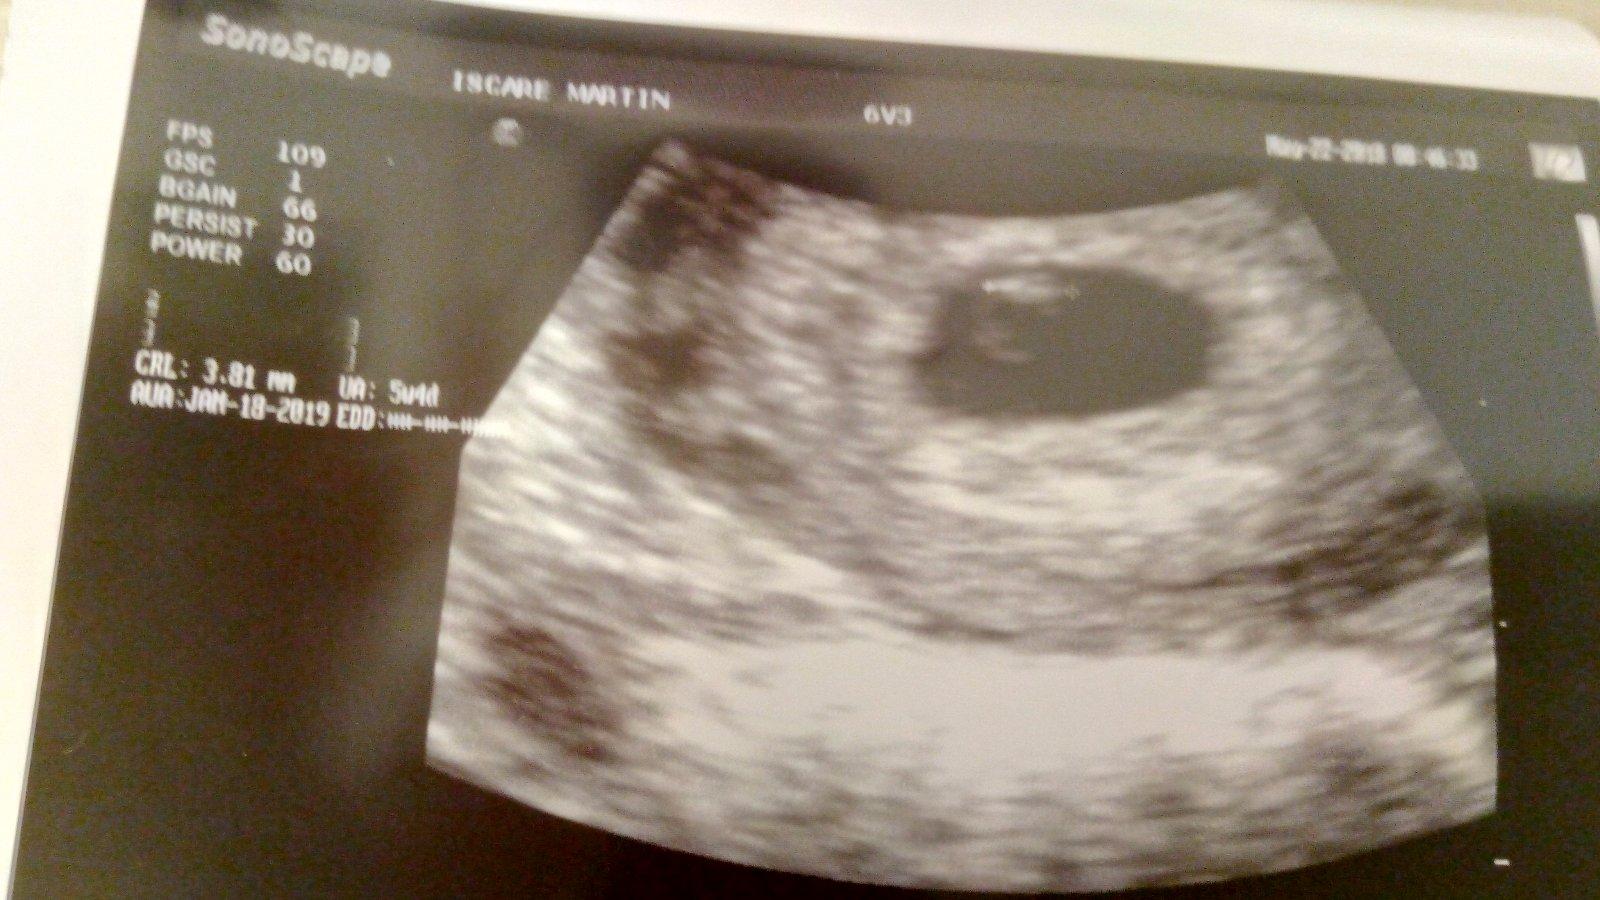

Dnes kontrola v Martine zatiaľ je všetko ok ale srdiečko ešte nebolo počuť že je zavčasu 5t4d snáď všetko bude ako má byť kontrola o týždeň a Vám ostatným dievčatám držím palce a budem na vás myslieť sme jeden tím a zvládneme to všetky do úspešného konca nikdy som tu nechodila až sama so sebou som už nevedela čo som sa išla kuknúť sem a som rada mám vás všetky rada spoznala som tiež jednu skvelú osobu zvedavá cica pomáha mi deno denne prežiť v kľude 😘😍😗😙😚